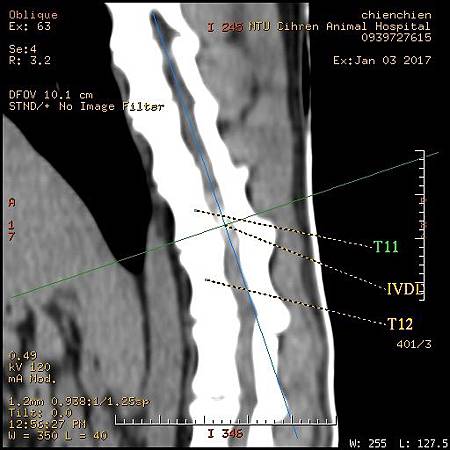

1. 臘腸 IVDD椎間盤突出

3. 臘腸IVDD 椎間盤突出